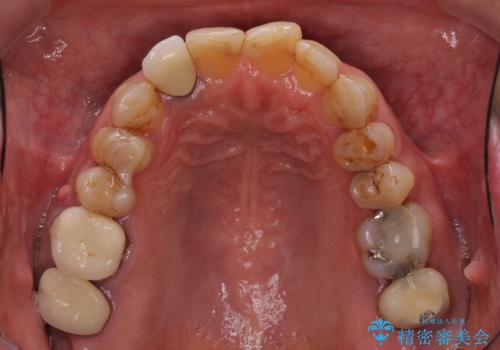

- 前歯のデコボコや、奥歯を咬んだときに痛みがあるとのことで来院された患者様です。

全体的に問題が多く、全てをしっかりと治療したいとのことでした。

全体的に中等度の歯周病と診断されたため、歯周外科処置やインプラントによる咬合回復から進めて行き、矯正治療による歯列改善を行った後にオールセラミッククラウンにて補綴することとしました。

矯正治療を希望して来院されましたが、歯周病を併発していたため、矯正治療開始前の処置が非常に多くなりました。特に歯槽骨の再生治療を行ったため、外科処置後の静置期間が長くなり、4年弱の治療期間となりました。